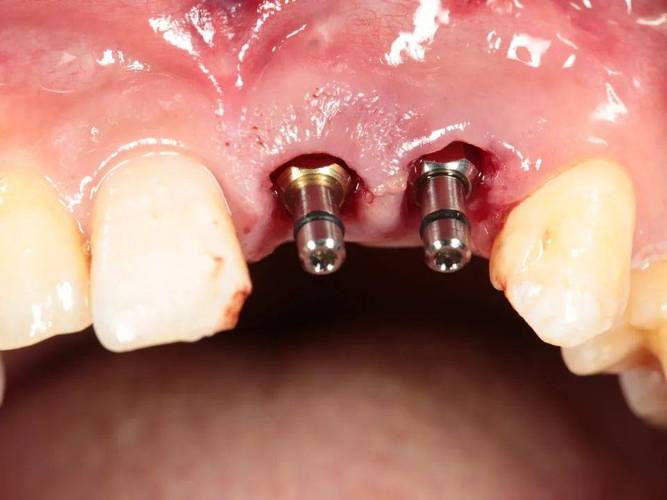

手术植入是种植牙的关键步骤,在局部麻醉下,医生切开牙龈,暴露牙槽骨,使用专用种植机将种植体植入预定位置,随后缝合牙龈,手术时间通常为30分钟-2小时(根据种植数量而定),过程中患者无明显疼痛,术后需服用抗生素预防感染,7-10天拆线,期间避免食用过硬、过热食物。

戴牙冠阶段通常在种植体植入后3-6个月,此时牙槽骨与种植体已完成骨结合,医生会取模,制作个性化的全瓷牙冠或烤瓷牙冠,并通过基台与种植体连接,完成最终的牙齿修复,牙冠的颜色、形态会与邻牙保持一致,达到以假乱真的效果。